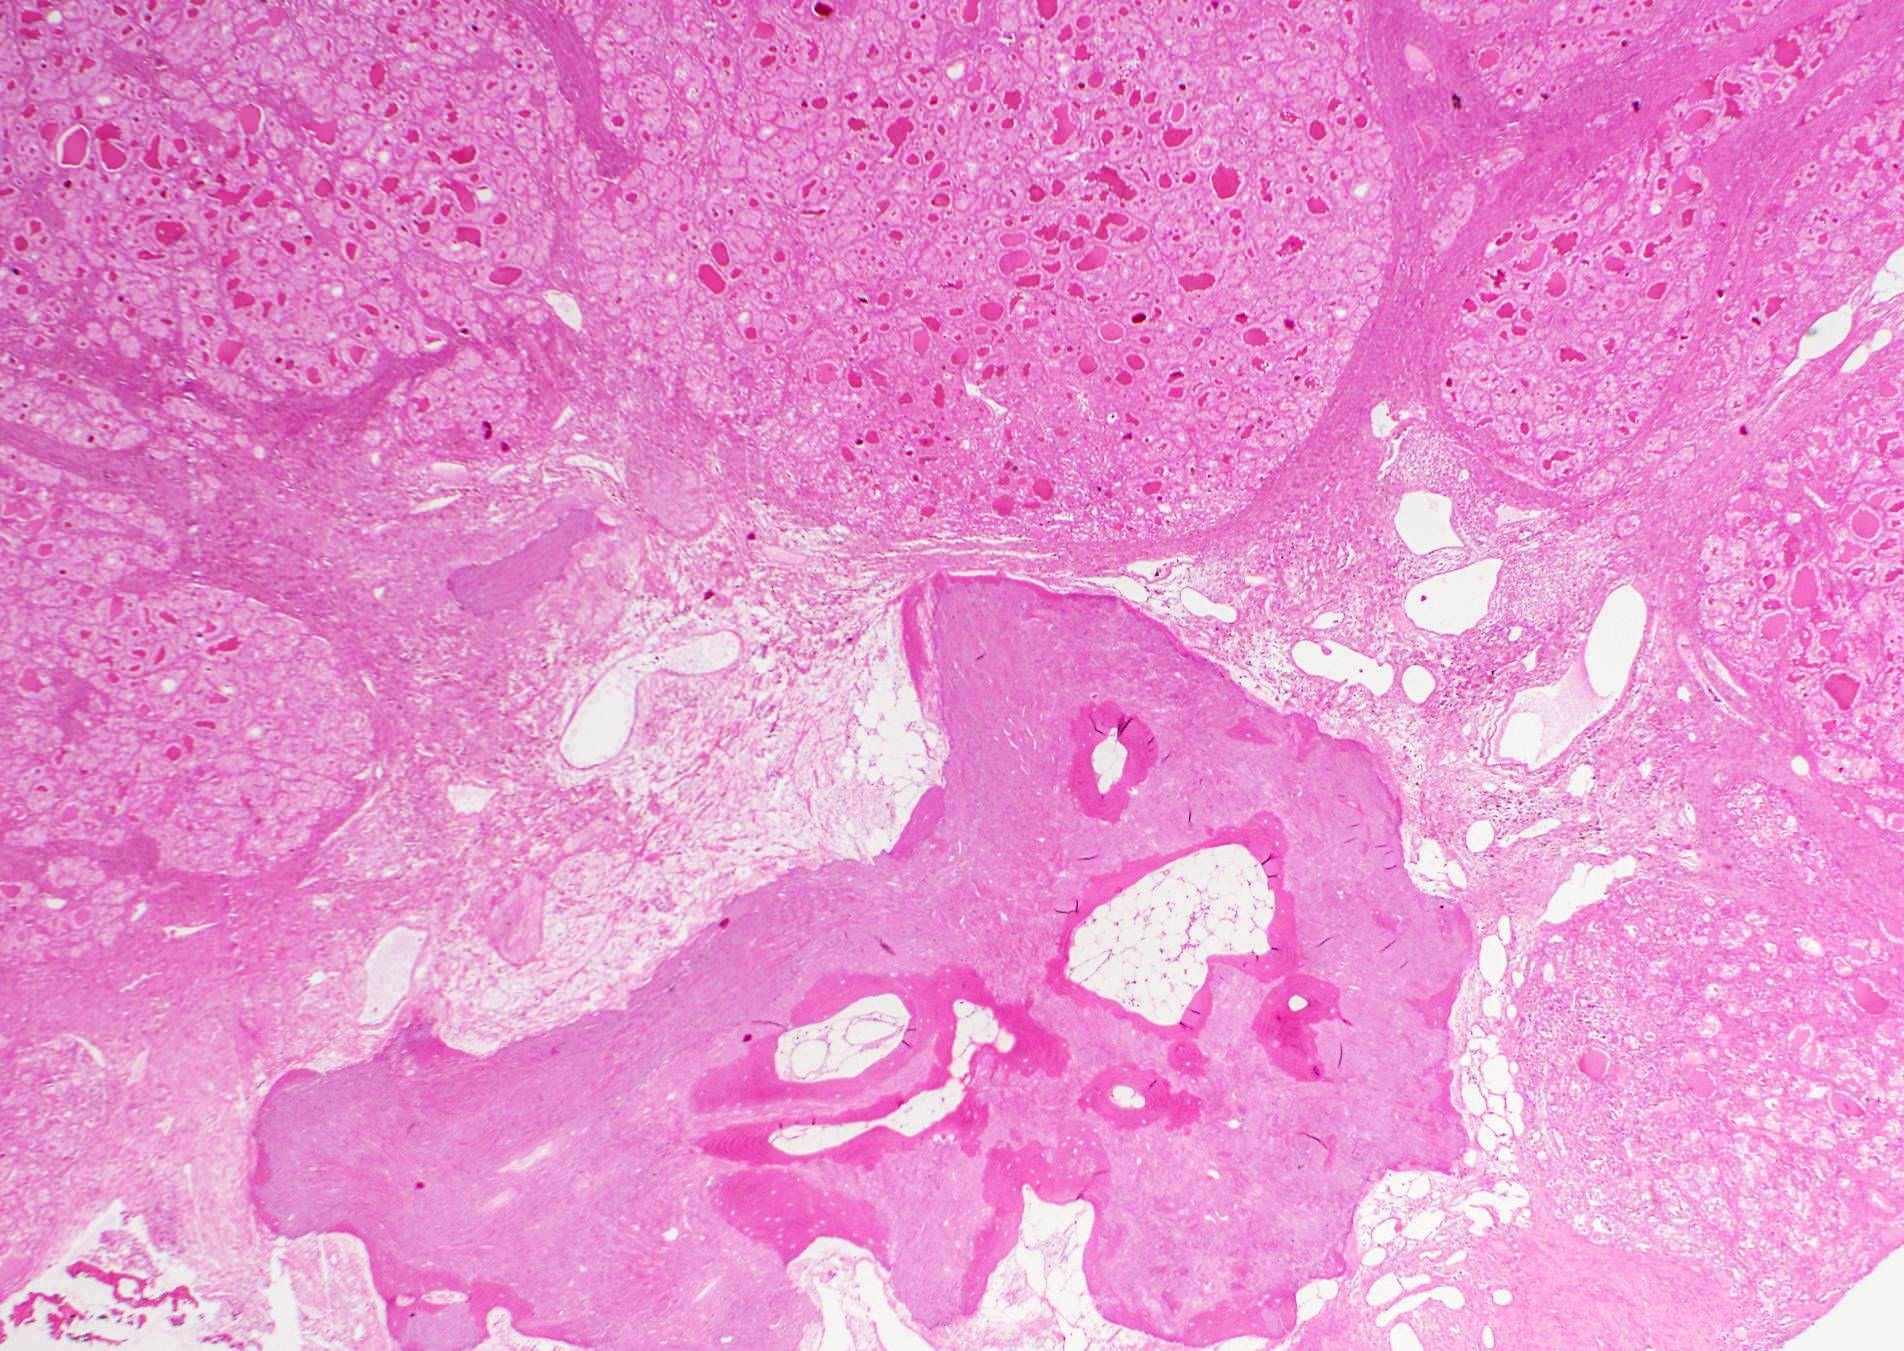

Microscopic (histologic) description

- Nuclear features of papillary thyroid carcinoma should be seen multifocally (at least 2 foci) or diffusely within the tumor; such features include nuclear enlargement, nuclear overlapping, chromatin clearing, nuclear membrane irregularity and nuclear grooves (J Clin Endocrinol Metab 2017;102:15)

- Nuclear score 2 - 3 (JAMA Oncol 2016;2:1023)

- Nuclear pseudoinclusion, a feature commonly seen in classic and tall cell variant, is rarely present in follicular variant

- Architecture: exclusively or nearly exclusively follicular

- True papillae with fibrovascular core are in general absent in follicular variant

- Tumors with mixed papillary (≥ 1% of total tumor volume) and follicular architecture should be classified as classic PTC with predominant follicular pattern, given the associated risk of lymph node metastasis (Thyroid 2019;29:1792)

- Solid architecture may be present: tumors with mixed follicular and solid architecture should be classified as follicular variant, whereas those with (almost) exclusive solid growth are classified as solid variant

- Encapsulated follicular variant has a complete fibrous tumor capsule or a well circumscribed tumor border

- Infiltrative follicular variant shows infiltrative or multinodular growth

- Sprinkling sign refers to the phenomenon that neoplastic follicles are seen scattered within the background of normal follicles

- "Bubble gum colloid", i.e. dense homogenous hypereosinophilic colloid, may be seen in the lumen of neoplastic follicles; scalloping of colloid may be seen

- Psammoma bodies are exceedingly rare in follicular variant; the identification of psammoma body should promote a search for true papillary (classic) area within the tumor

Microscopic (histologic) images